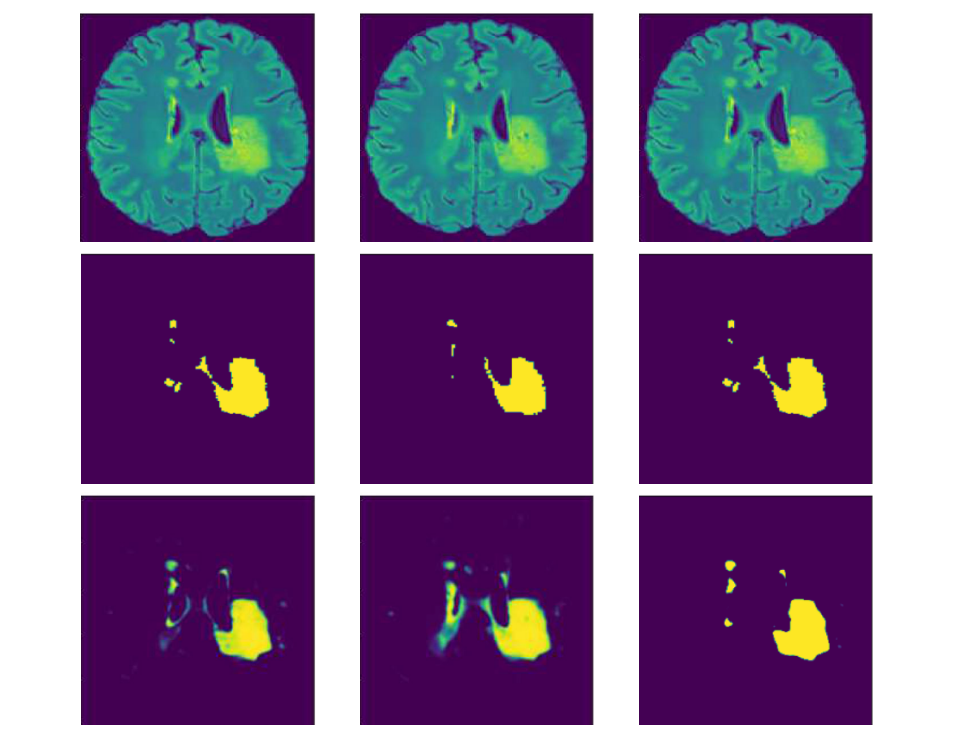

Automated Multi-Class Brain Glioma Segmentation Using Cascaded mLinkNet

Glioma is one of the most common and vigorous tumors of the brain, which may lead to a very short life expectancy. There has been considerable interest in the potential of the non-invasive Magnetic Resonance Imaging

Glioma is one of the most common and vigorous tumors of the brain, which may lead to a very short life expectancy. There has been considerable interest in the potential of the non-invasive Magnetic Resonance Imaging (MRI) to aid the clinician in diagnosis, determination of the tumor extent, treatment planning, and disease management. Automated brain glioma segmentation from MR modalities remains a challenging, time-consuming, computationally intensive, and error-prone task till date. This paper introduces an automatic technique for the diagnosis of brain tumor regions from multi-class brain MRI using a modified version of LinkNet (mLinkNet) based on Convolutional Neural Networks (CNNs), where three types of deep CNN models were trained: W-mLinkNet, C-mLinkNet, and E-mLinkNet. The multiclass segmentation problem has been decomposed into three steps of binary segmentation of the glioma regions, i.e., Whole tumor, Tumor core, Enhancing tumor core, by cascading the above models one after the other in sequence. We also investigated the use of zero-centering and normalization of intensity for smooth variation of the intensity over the tissues as a pre-processing step. A relative study has been done to prove the efficacy of the proposed CNN model on the Brain Tumor Segmentation Challenge 2015 database (BraTS 2015).